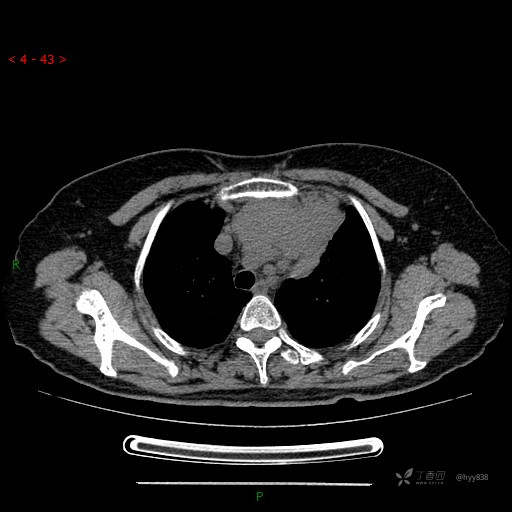

简要病史:患者诉3月余前患新冠肺炎,出现持续性胸闷,活动后可缓解,无胸前区压榨感,无畏寒发热不适,无胸痛咯血、呼吸困难,无恶心、呕吐,无腹痛、腹胀、腹泻等不适,未予以重视,未行特殊处理。患者胸闷持续存在,为进一步诊治,3天前于本院查胸部CT提示前纵膈团块状软组织密度影,肿瘤性病变可能,心包积液,左上肺磨玻璃结节,右下肺增殖灶可能建议进一步检查。门诊以“前纵膈占位” 收入我科。 患者本次起病来精神、食欲、睡眠尚可,大小便正常,体力、体重无明显变化。

辅助检查:CT

临床诊断:纵隔占位

胸部CT平扫